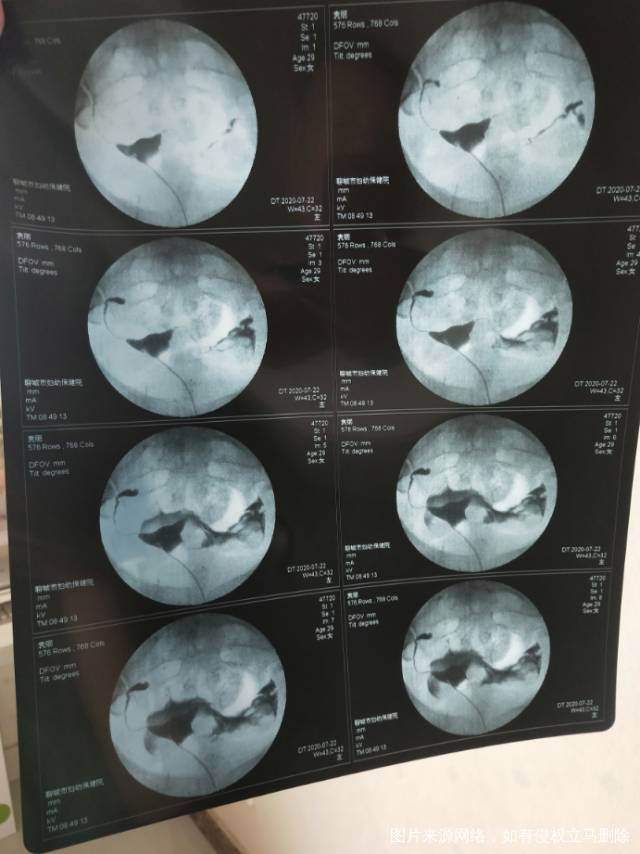

两年前自然流产后一直未怀孕这是做的造影片子请

两年前自然流产后一直未怀孕,这是做的造影片子,请大夫帮忙看下给个建议